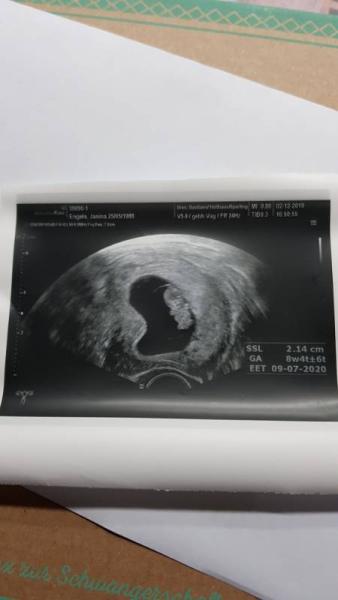

Guten Morgen Zusammen, ich hatte gestern bei 8+4 einen Termin beim FA. So nervös war ich glaube ich noch nie. Umso schöner, dass alles in Ordnung ist. Ich konnte unseren kleinen Teddybären gut erkennen. Er hat sich bewegt und sah wirklich aus wie ein Kuscheltier. Zwei Tage wurde ich zurückdatiert Der errechnete Termin ist jetzt der 09.07.20 Nächster Termin ist am 30.12. Freue mich so sehr, dass alles in Ordnung ist!!!

Bild zu Ein Teddybär - Forum für Juli - Mamis